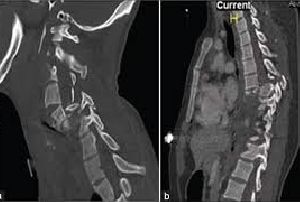

Radiografia Della Colonna Vertebrale Rmi Del Collo E Testa Di Stress Fotografie Stock E Altre Immagini Di Adulto Istock

Immagini Stock Radiografia Del Collo E Del Rachide Cervicale Test Funzionale Laterale Lat Instabilita Image

Radiografia Della Colonna Vertebrale Rmi Del Collo E Testa Di Stress Fotografie Stock E Altre Immagini Di Collo Umano Istock

Radiografia Della Colonna Cervicale Con Proiezioni Dinamiche Iltuoesame It